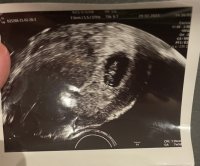

Hva tror dere? Innvendig uke 6+0

Dette bildet er fra innvendig mellom uke 7 og 8.